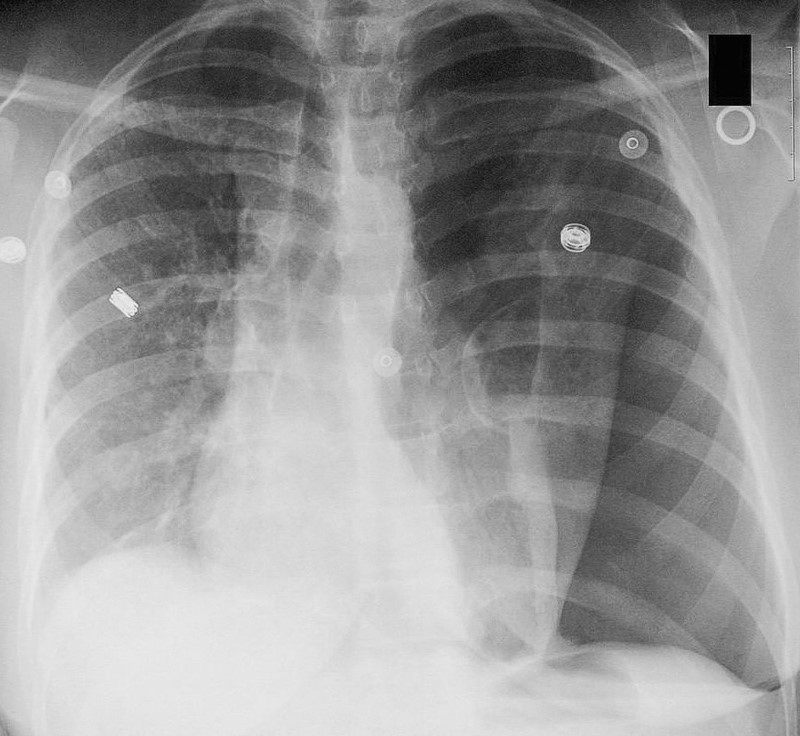

Después de la sorpresa inicial, se detiene a mirar la radiografía. ¿Qué puede ver en ella?